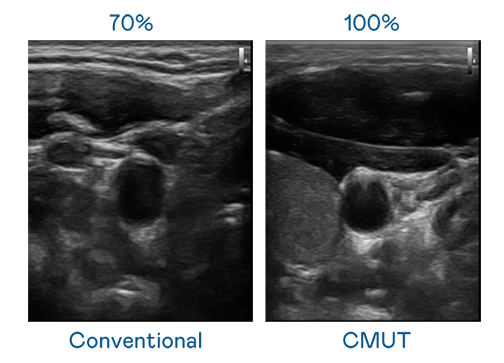

CMUT 技术是一种用电容式微机电元件来产生超音波讯号的技术。与传统 PZT 压电式技术相比,CMUT 频宽增加 30%,更宽频的超音波讯号让影像解析度大幅提升,是实现高影像品质医疗超音波扫描、促进精准医疗发展的关键技术。

大频宽带来超清晰影像

超音波影像的解析度高低,首先取决于探头能发出的讯号频宽。AG旗舰厅 CMUT 可提供高清晰的超音波讯号,提供高频宽、高灵敏度、影像纹理细节更高的超音波影像,协助医护人员缩短影像判读时间及利用精准的医疗影像进行诊断。